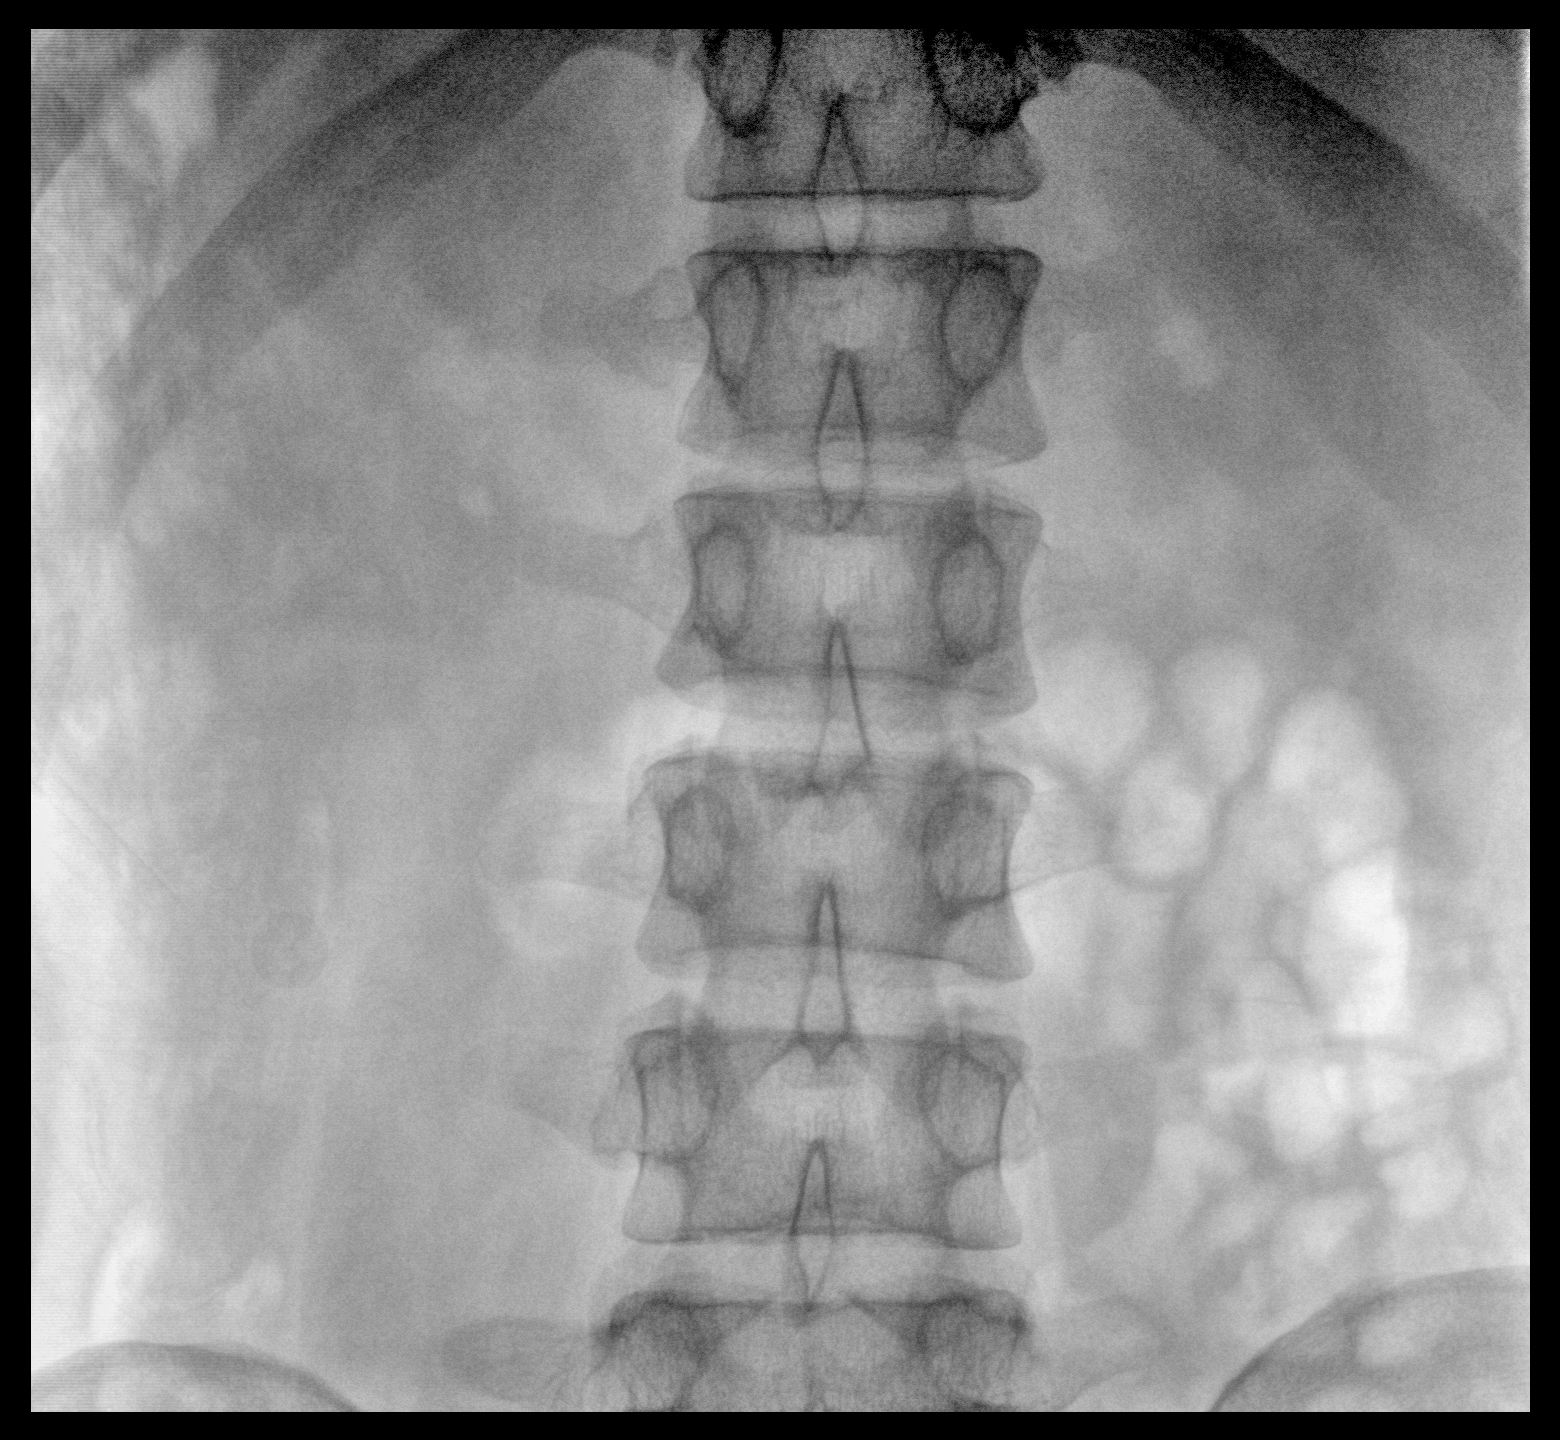

PLX118F-Plus配備了兩種平板尺寸,大尺寸動(dòng)態(tài)平板探測(cè)器成像面積較傳統(tǒng)平板探測(cè)器提升了25%以上,在視野需求大的手術(shù)中,便于醫(yī)生更好定位病灶點(diǎn),規(guī)劃手術(shù)方案,減少因視野范圍不足而多次透視、點(diǎn)片造成的不便。